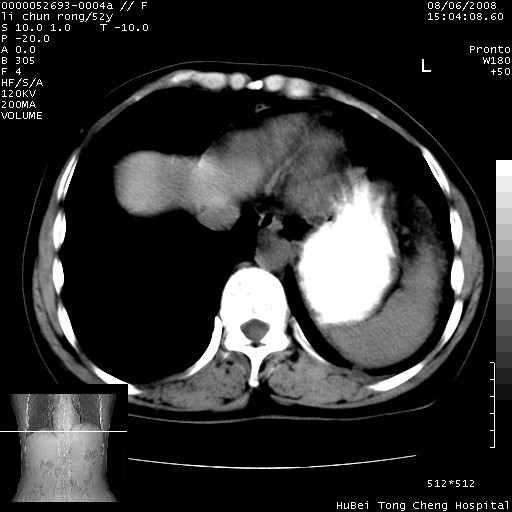

以下是引用云翔在2008-8-7 6:20:00的发言:[br]胰尾部囊性病变,考虑假囊肿,结合实验室检查疾病史

以下是引用zjzjr在2008-8-7 8:38:00的发言:[br]支持胰腺炎伴假囊肿形成,左肾小囊肿.少量腹水.

以下是引用随光逐影在2008-8-7 9:12:00的发言:[br]1)考虑胰腺炎伴假性囊肿形成可能性大;胰腺囊腺瘤待排。2)左肾小囊肿。3)少量腹水。